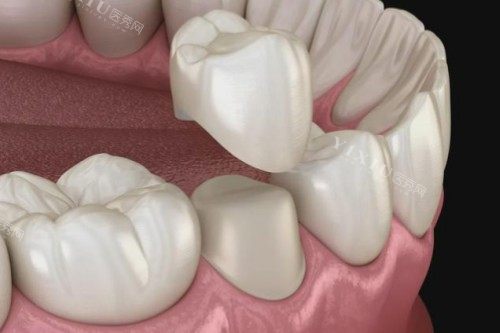

种植牙:采用韩国登腾、瑞士ITI等国内外老牌种植系统,单颗种植牙2980元起,全口种植牙8万元起,支持All-on-4即刻种植技术,当天即可修养咀嚼功能。

种植牙:单颗2980元起,半口5万元起